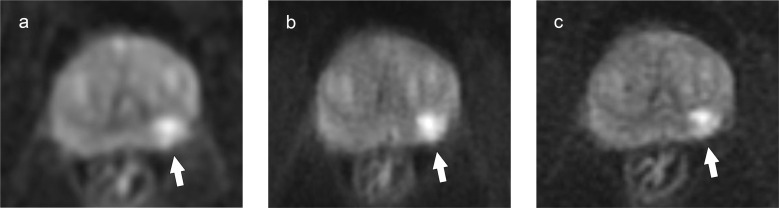

Purpose: To compare objective and subjective image quality, lesion conspicuity, and apparent diffusion coefficient (ADC) of high-resolution multiplexed sensitivity-encoding diffusion-weighted imaging (MUSE-DWI) with conventional DWI (c-DWI) and reduced FOV DWI (rFOV-DWI) in prostate MRI.

Methods: Forty-seven patients who underwent prostate MRI, including c-DWI, rFOV-DWI, and MUSE-DWI, were retrospectively evaluated. SNR and ADC of normal prostate tissue and contrast-to-noise ratio (CNR) and ADC of prostate cancer (PCa) were measured and compared between the three sequences. Image quality and lesion conspicuity were independently graded by two radiologists using a 5-point scale and compared between the three sequences.

Results: The SNR of normal prostate tissue was significantly higher with rFOV-DWI than with the other two DWI techniques (P ≤ 0.01). The CNR of the PCa was significantly higher with rFOV-DWI than with MUSE-DWI (P < 0.05). The ADC of normal prostate tissue measured by rFOV-DWI was lower than that measured by MUSE-DWI and c-DWI (P < 0.01), while there was no difference in the ADC of cancers. In the qualitative analysis, MUSE-DWI showed significantly higher scores than rFOV-DWI and c-DWI for visibility of anatomy and overall image quality in both readers, and significantly higher scores for distortion in one of the two readers (P < 0.001). There was no difference in lesion conspicuity between the three sequences.

Conclusion: High-resolution MUSE-DWI showed higher image quality and reduced distortion compared to c-DWI, while maintaining a wide FOV and similar ADC quantification, although no difference in lesion conspicuity was observed.